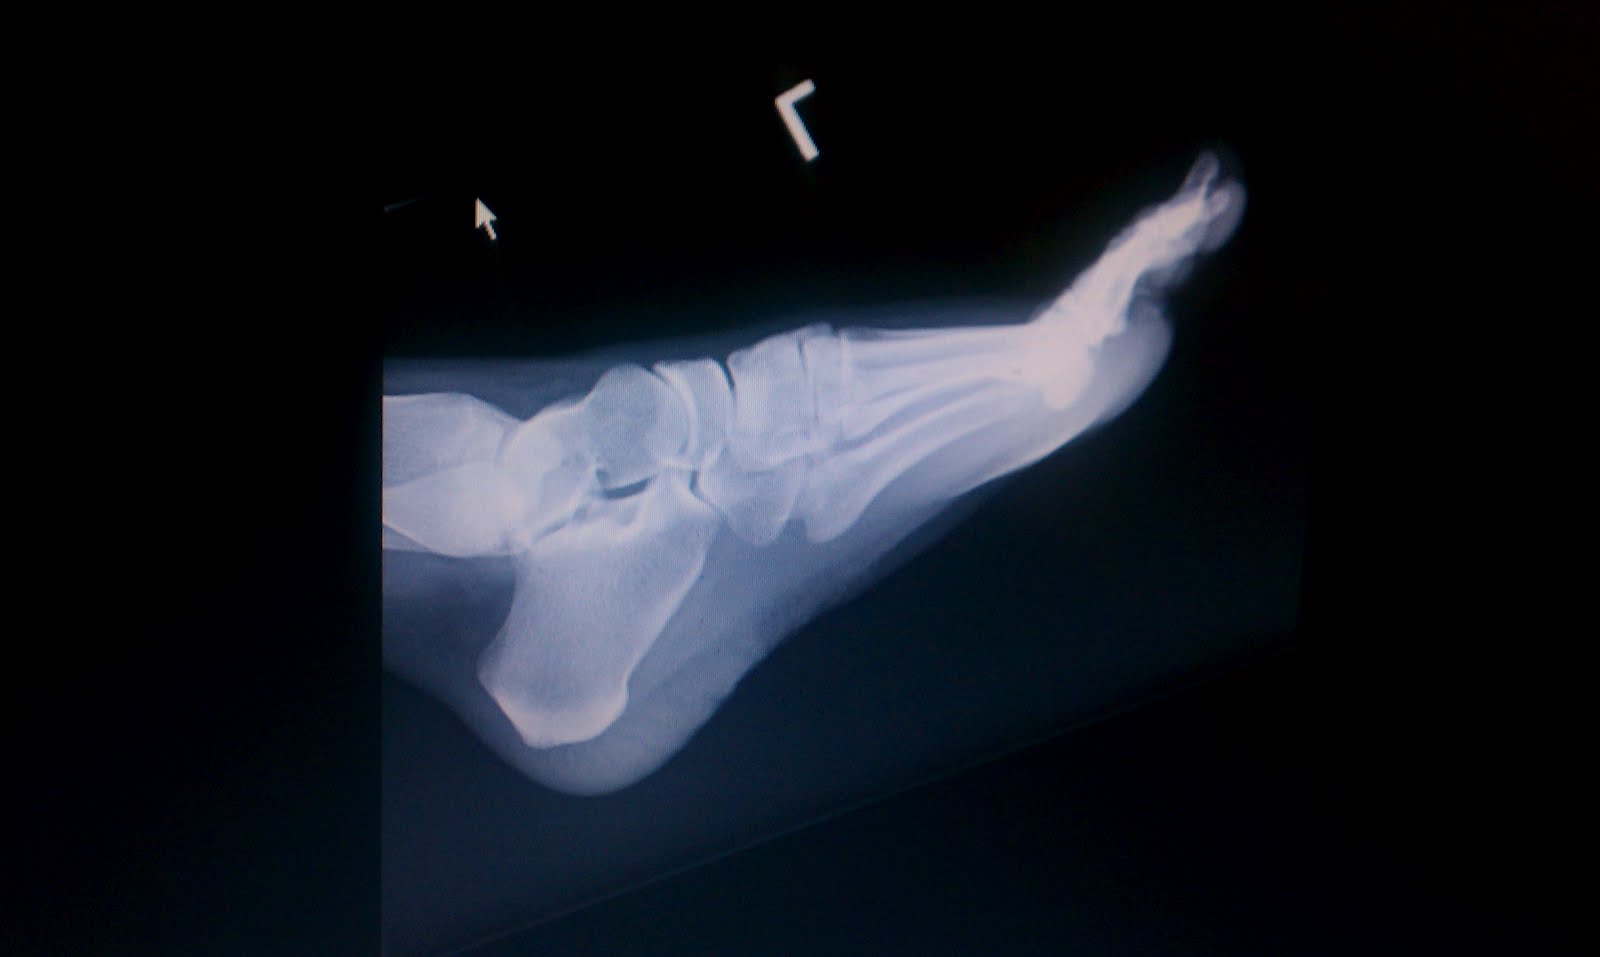

Conclusion - a severe sprain. They took a bunch of x-rays and the Dr believes there are no fractures or breaks, but the radiologist will call me today to confirm or give his opinion. I broke a blood vessel on the side and it formed an ugly bulge and is causing some extra pain. I was put in a walking boot and told to keep my foot up as much as possible, ice it, then heat pack it, then ice it again, pretty much all day for the first few days and then we will have to see how it heals.